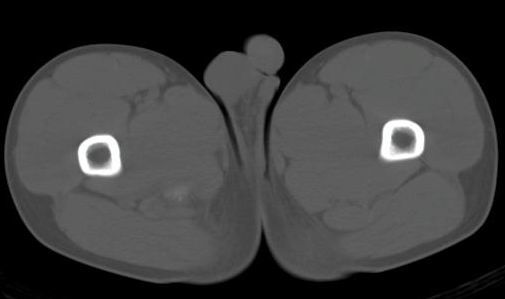

男性,15岁,半年前曾有做运动摔伤史,伤后左肢麻木,一天后恢复,两个月后因右臀部隐痛照片示右坐骨下骨性密度影,现复查见骨性影无明显改变。求助诊断!

如果是撕脱骨折,应该有疼痛,而病史是伤后左肢麻木,一天后恢复,两个月后因右臀部隐痛才就诊,病变在肌肉区,故考虑骨化性肌炎

如果是撕脱骨折,症状不支持。两个月后因右臀部隐痛才就诊,病变在肌肉区,故考虑骨化性肌炎

应该没有骨折,骨化性肌炎.